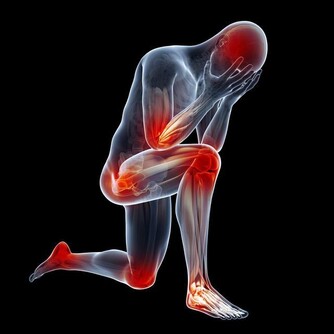

近十幾年來,生薑在紓緩疼痛、輔助治療關節炎上的效果倍受矚目。

風濕病專家在250名骨關節炎患者中進行過一項實驗:

在6週的療程中,一組患者每天兩次服用含有生薑成分的藥物255毫克,另一組患者則服用不含生薑成分的藥物。

2/3服用了含有生薑成分藥物的患者反映,他們感覺病痛減輕,其效果遠遠高於另一組的患者。